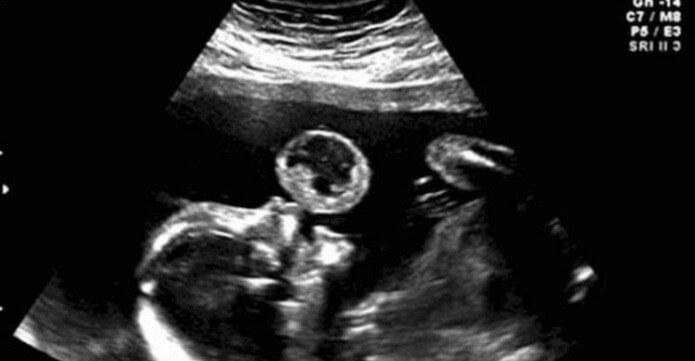

Tammy Gonzales från Miami, upptäckte på ett rutinmässigt ultraljud någonting som liknar en stor bubbla som kom ut ur hennes barns mun.

Efter ytterligare en undersökning avslöjades det att bubblan i bilden var något som kallas för teratom, vilket är en extremt sällsynt och vanligtvis dödlig tumör.

Tammy kunde andas lätt när hon såg tumören glida bort från barnets ansikte på ultraljudsbilden. Även om tumören var för stor för att ta bort genom fostret, var den inte längre skadlig för barnet och mamman. Tumören blev därför flytande i livmodern fram till födseln.